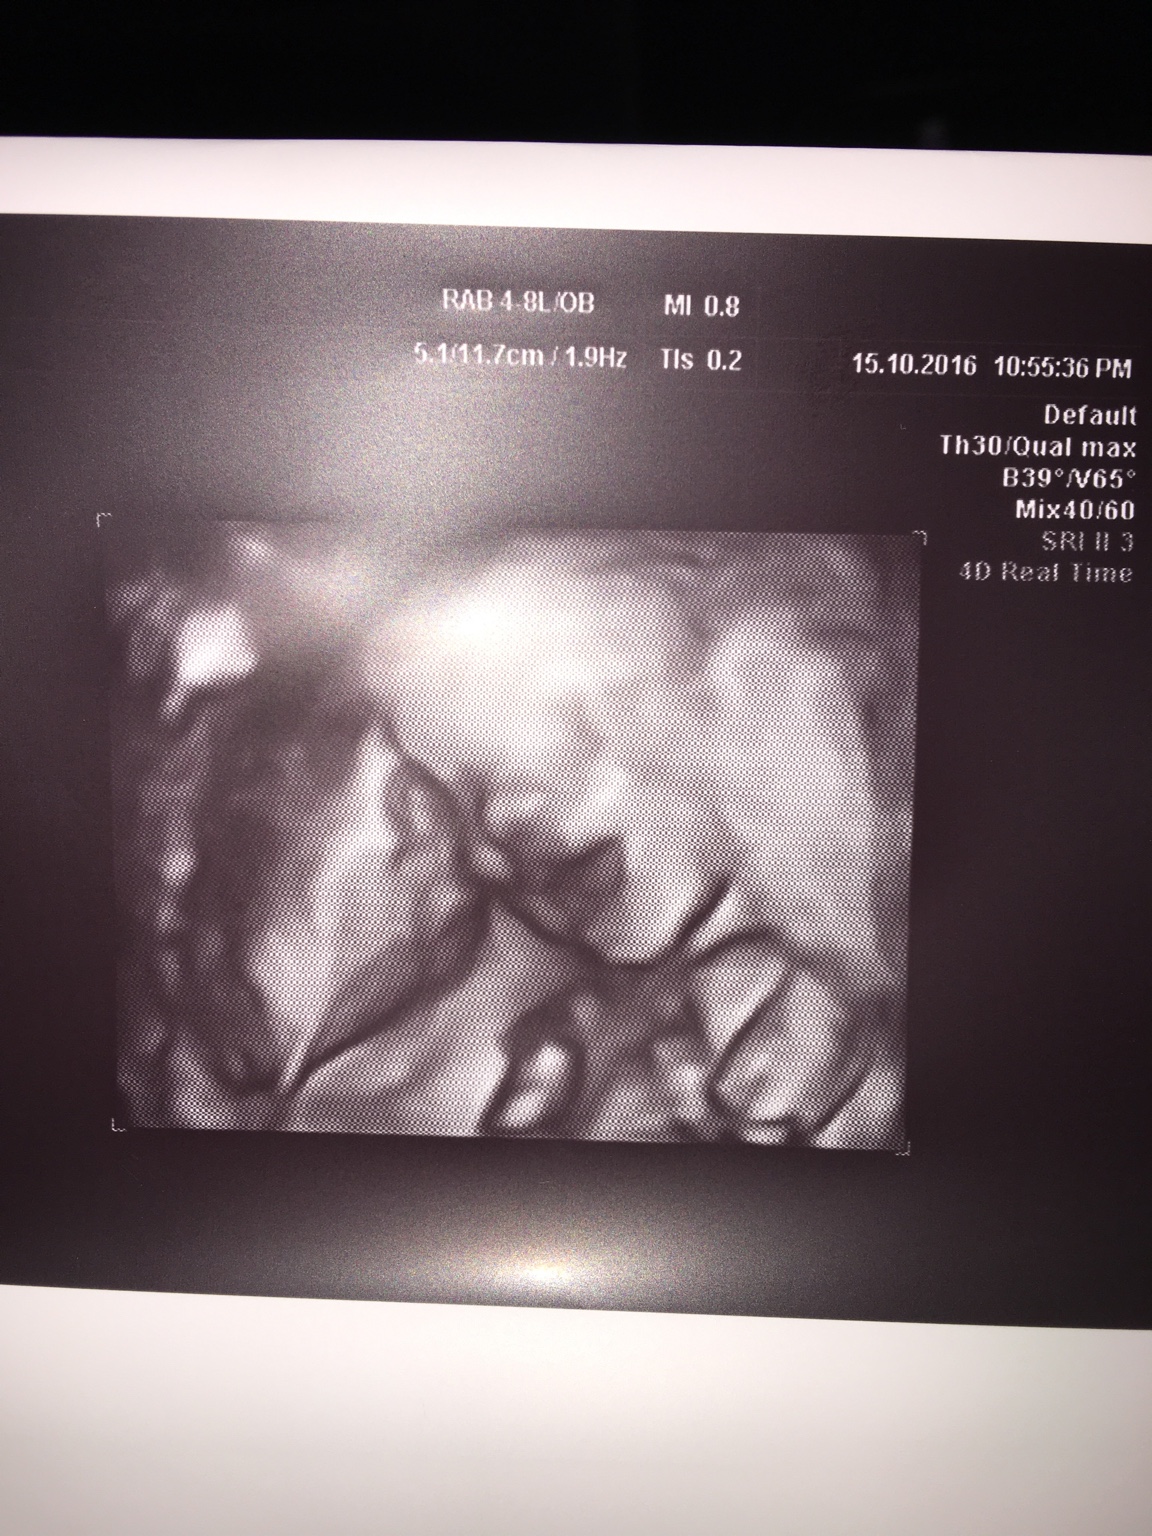

Uśmiechnięty Antoś [emoji173]️